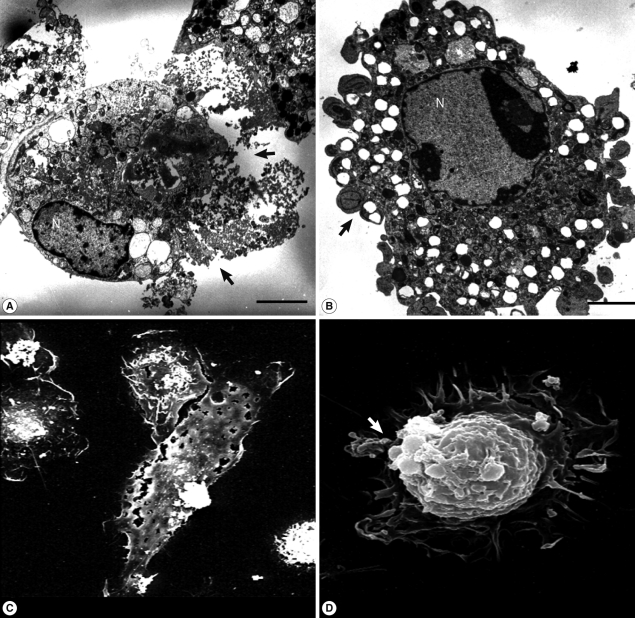

N. fowleri lysate (1 mg/ml) exerted severe morphological changes, including disruption and breakdown of the plasma membrane on the rat microglia, and significantly promoted cell death (Fig. 1). These effects were dose-dependent (Fig. 1). Microglial lethality was almost complete within 6 hr culture with N. fowleri lysate, generally appearing necrotic in nature and characterized by membrane swelling and lysis of the nuclear membrane and nucleus (Fig. 2A, 2C). Some microglial cells additionally evinced hallmarks of apoptosis, such as blebbing, formation of apoptotic bodies, and nuclear chromatin condensation (Fig. 2B, 2D). In previous reports, pathogenic Acanthamoeba culbertsoni lysate induced cytopathic effects, including necrosis and apoptosis, in primary rat microglial cells [21,22], suggesting that N. fowleri contact-independent cytotoxicity proceeds similarly.

TEM and SEM images of microglia treated with N. fowleri lysate. Microglial cells were treated with N. fowleri lysate (1 mg/ml) for 12 hr. Necrosis could be observed concomitantly with plasma membrane lysis (arrows; A, C), and programmed cell death with accompanying changes, including apoptotic bodies (arrows) and nuclear chromatin condensation (B, D). Bar=5 µm.

Fig. 2 TEM and SEM images of microglia treated with N. fowleri lysate. Microglial cells were treated with N. fowleri lysate (1 mg/ml) for 12 hr. Necrosis could be observed concomitantly with plasma membrane lysis (arrows; A, C), and programmed cell death with accompanying changes, including apoptotic bodies (arrows) and nuclear chromatin condensation (B, D). Bar=5 µm.